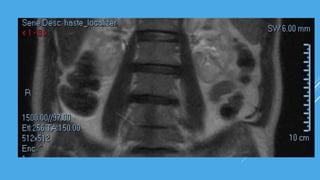

RMN

PROTRUSIÓN DISCAL ANTERIOR A NIVEL L1-L5, A NIVEL DE L4-L5 EXTRUSIÓN

DISCAL ANTERIOR CON OBSTRUCCIÓN NEUROFORAMIDAL CON MIGRACIÓN

CAUDAL BILATERAL QUE CONTACTA CON ESPACIO SUBDURAL ANTERIOR AL IGUAL

QUE A NIVEL DE L2-L3, SE VISUALIZA DISTESIS ANTERIOR A NIVEL DE L3 SOBRE L4

Y L4 SOBRE L5.